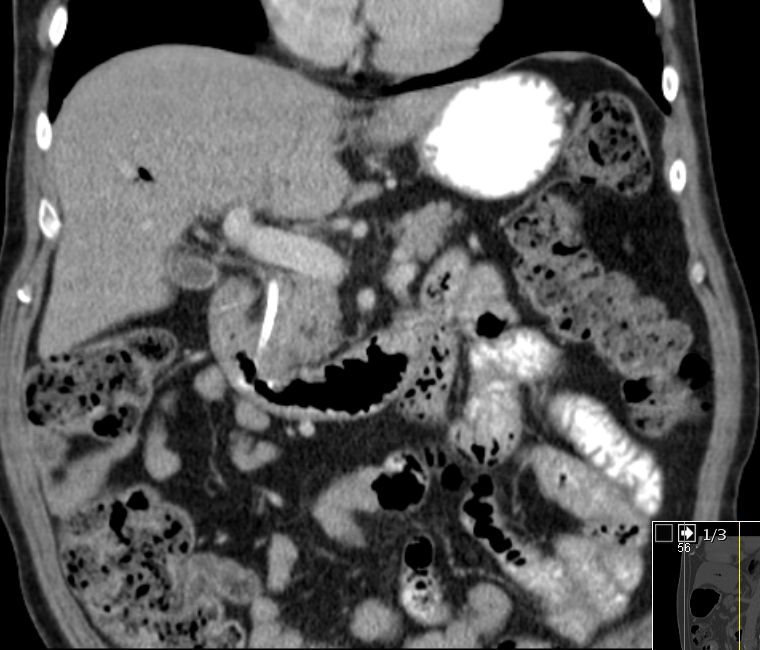

Colon 79-jährige Frau mit einem Tumor im Zoekum. Bei der Operation fand sich im Bereich der Ileozökalklappe ein unregelmäßig gestalteter, teils ulzerierter und teils polypös erhabener, 42 mm großer, derber Gewebsbezirk. Histologie: In soliden Komplexen und Strängen angeordnete, relativ große Tumorzellen mit deutlicher Zell- und Kernpolymorphie. Vergrößerte Zellkerne mit aufgelockerter Chromatinstruktur und ab und an prominenten Nukleolen. Schmaler oder kaum erkennbarer Zytoplasmasaum. Vermehrt typische und atypische Mitosen. Tumoreinbruch in Blut- und Lymphgefäße. Das CT zeigt multiple Lebermetastasen.